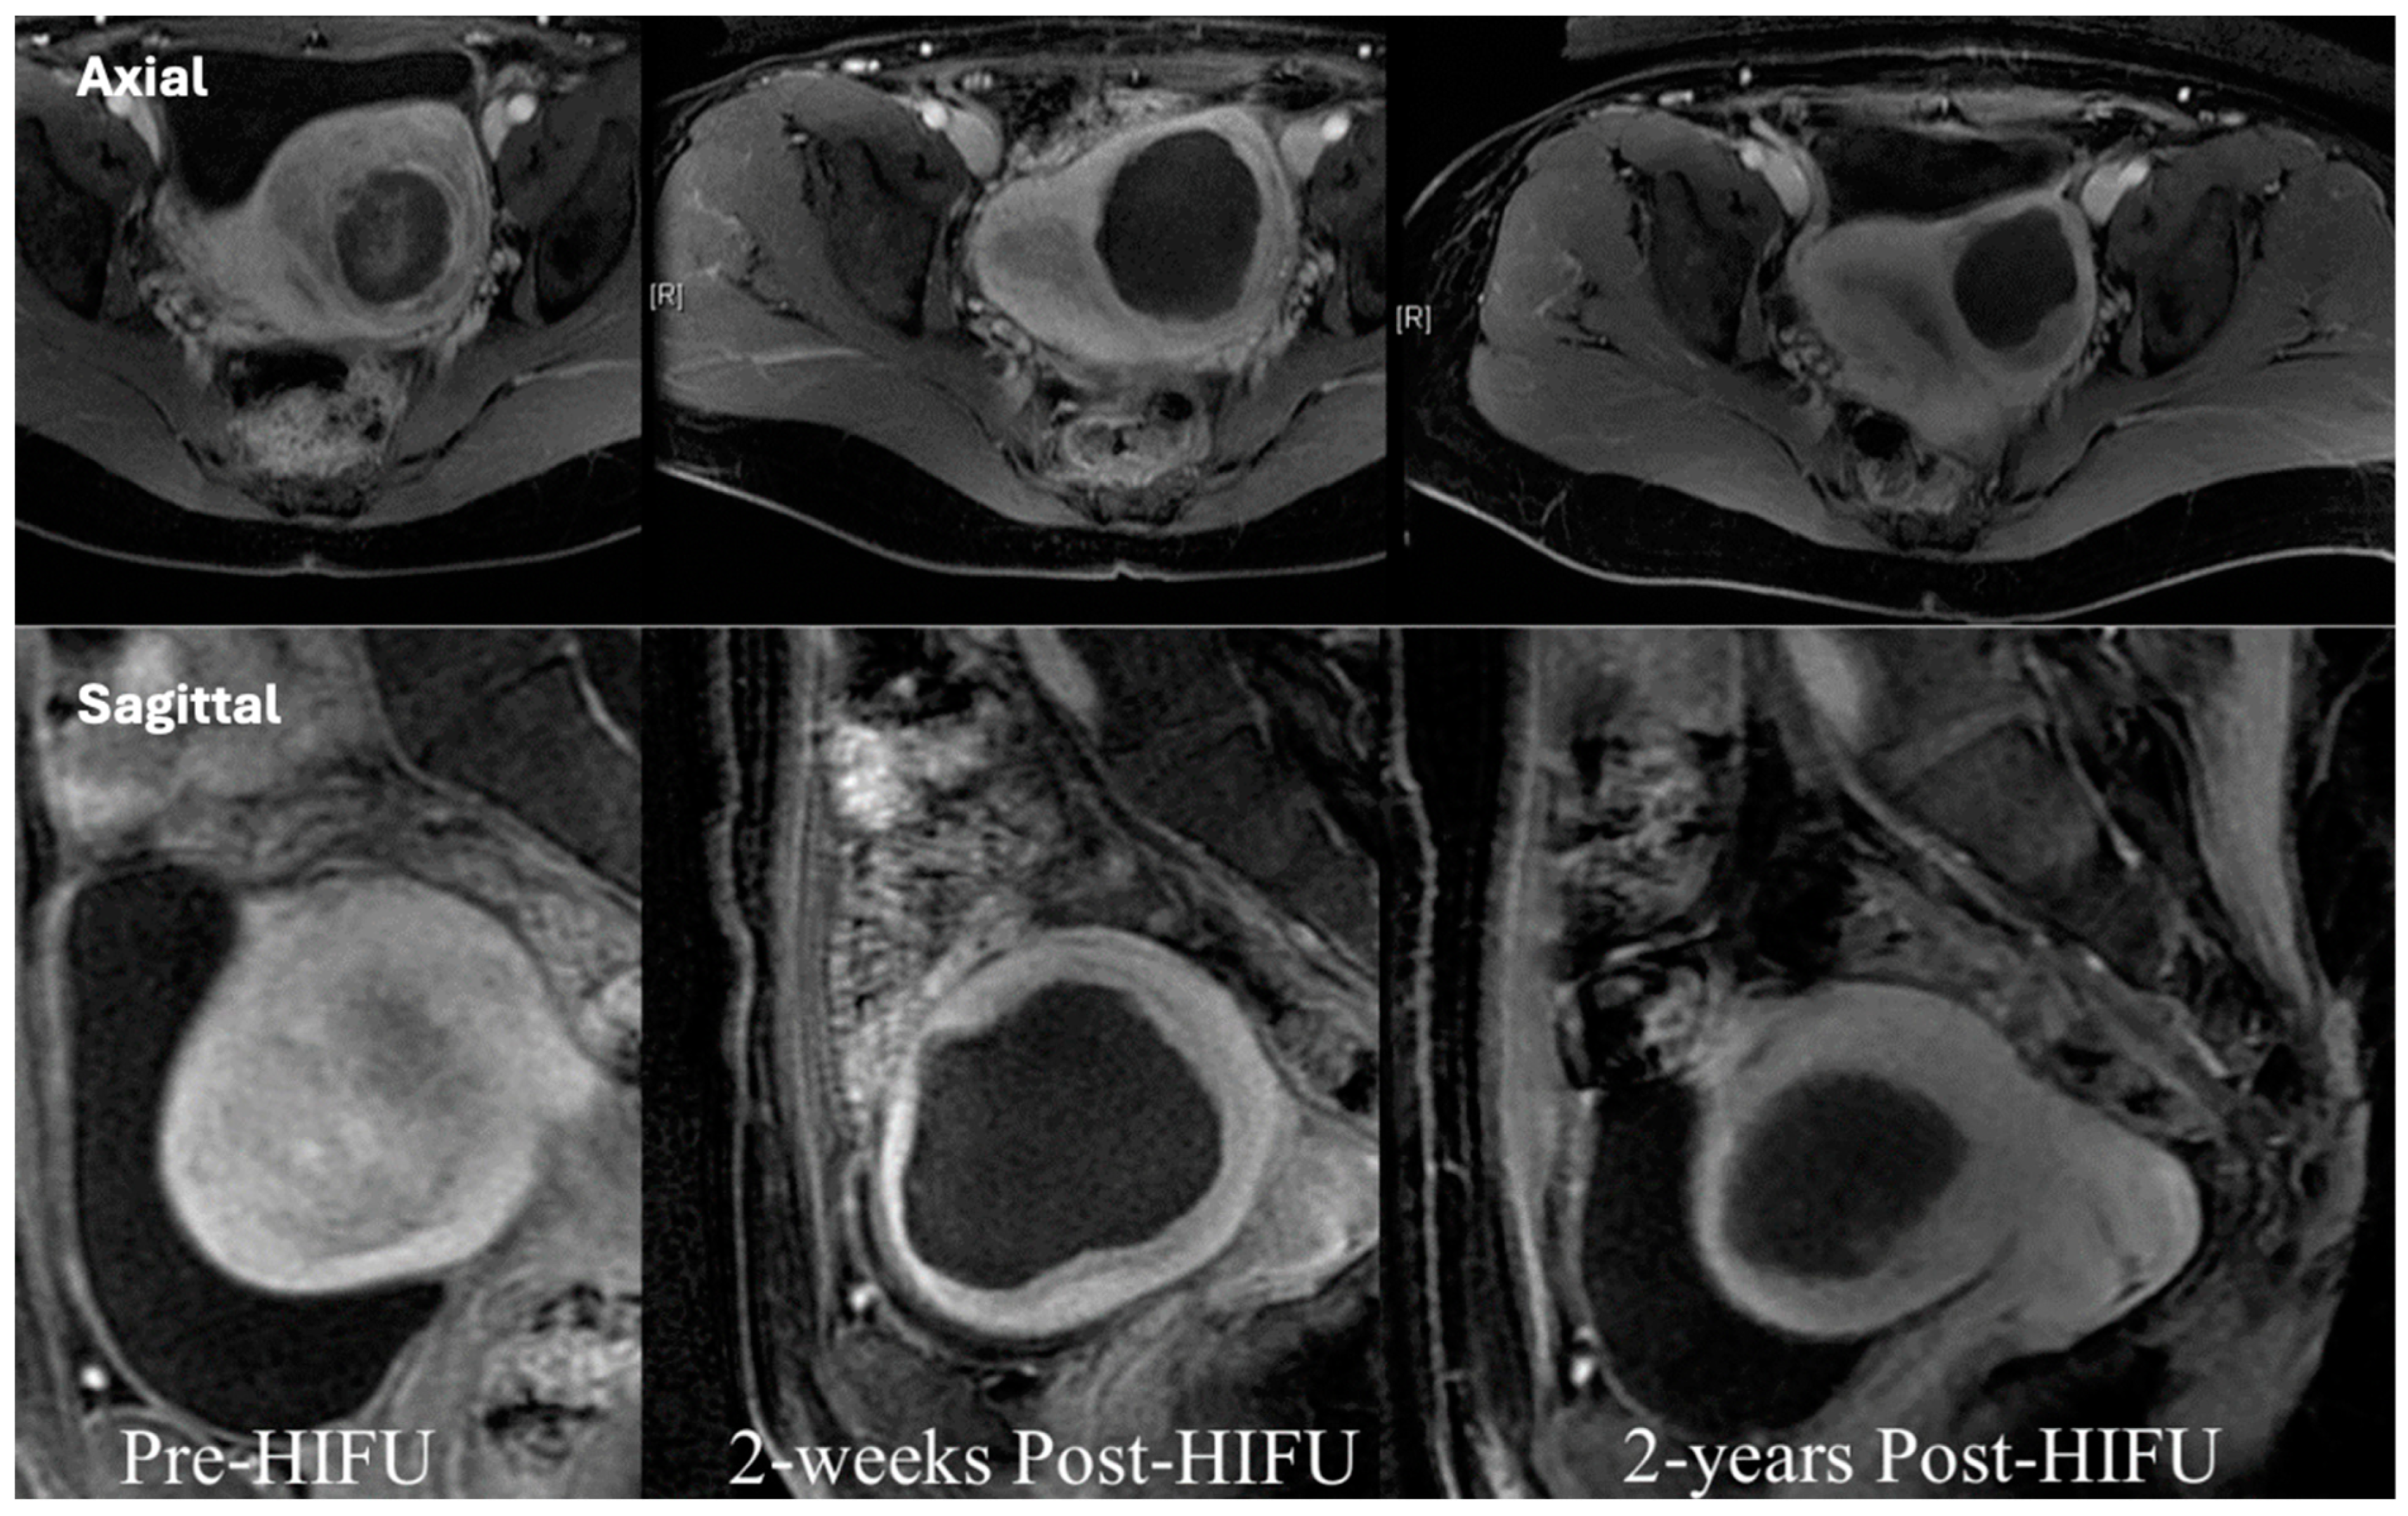

4.1. Kidney